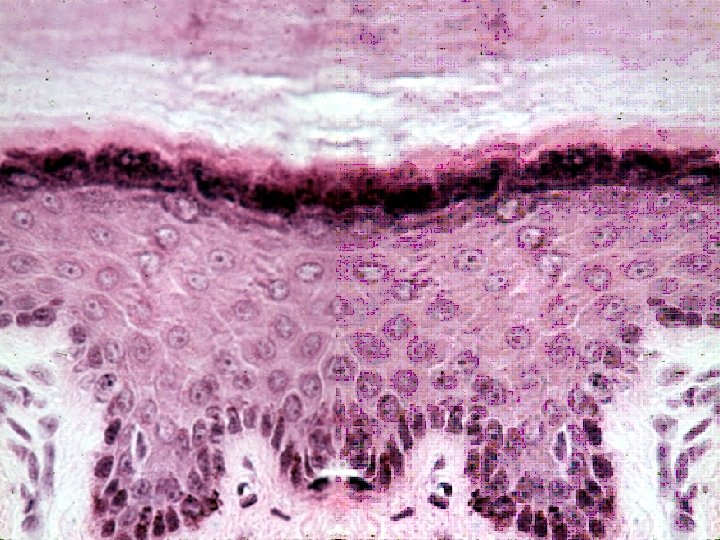

• Pseudostratified Columnar Epithelium lining Trachea. • H&E stain. Magnification 400 x. • Note the presence of cilia and goblet cells. The pointer indicates the mucus plug of a goblet cell. As this type of epithelium is formed of cells of varying height, one gets the impression of two rows of nuclei. This appearance is a characteristic that will help you to identify the pseudostratified epithelium from the upper respiratory tract. Another feature associated with pseudostratified columnar epithelium from the upper respiratory region is the presence of a prominent wide basement membrane.

• Pseudostratified Ciliated Columnar Epithelium with goblet cells lining the Trachea. • H&E stain. Magnification 600 x. • The pointer indicates a broad basement membrane.